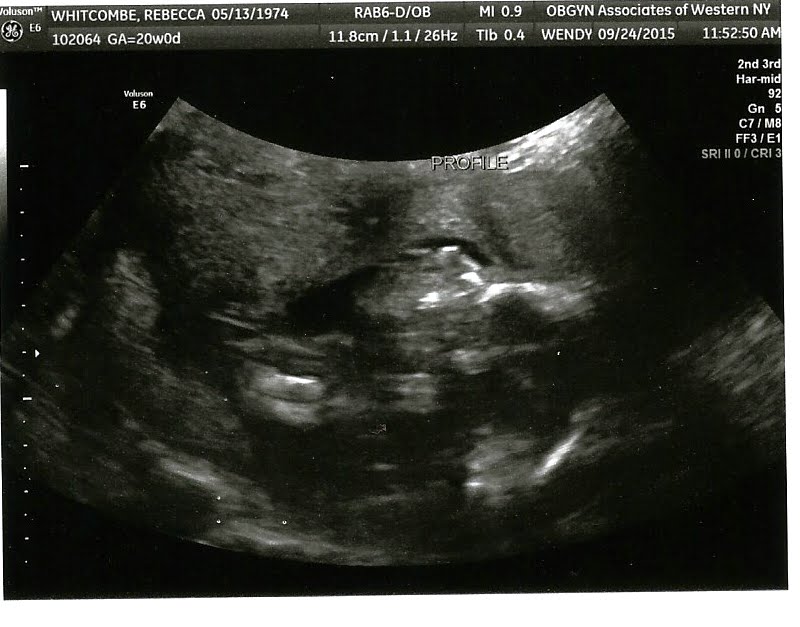

Another week.....another Ultrasound

More fluid this week and all is well at 20 weeks (half way there maybe, maybe less)